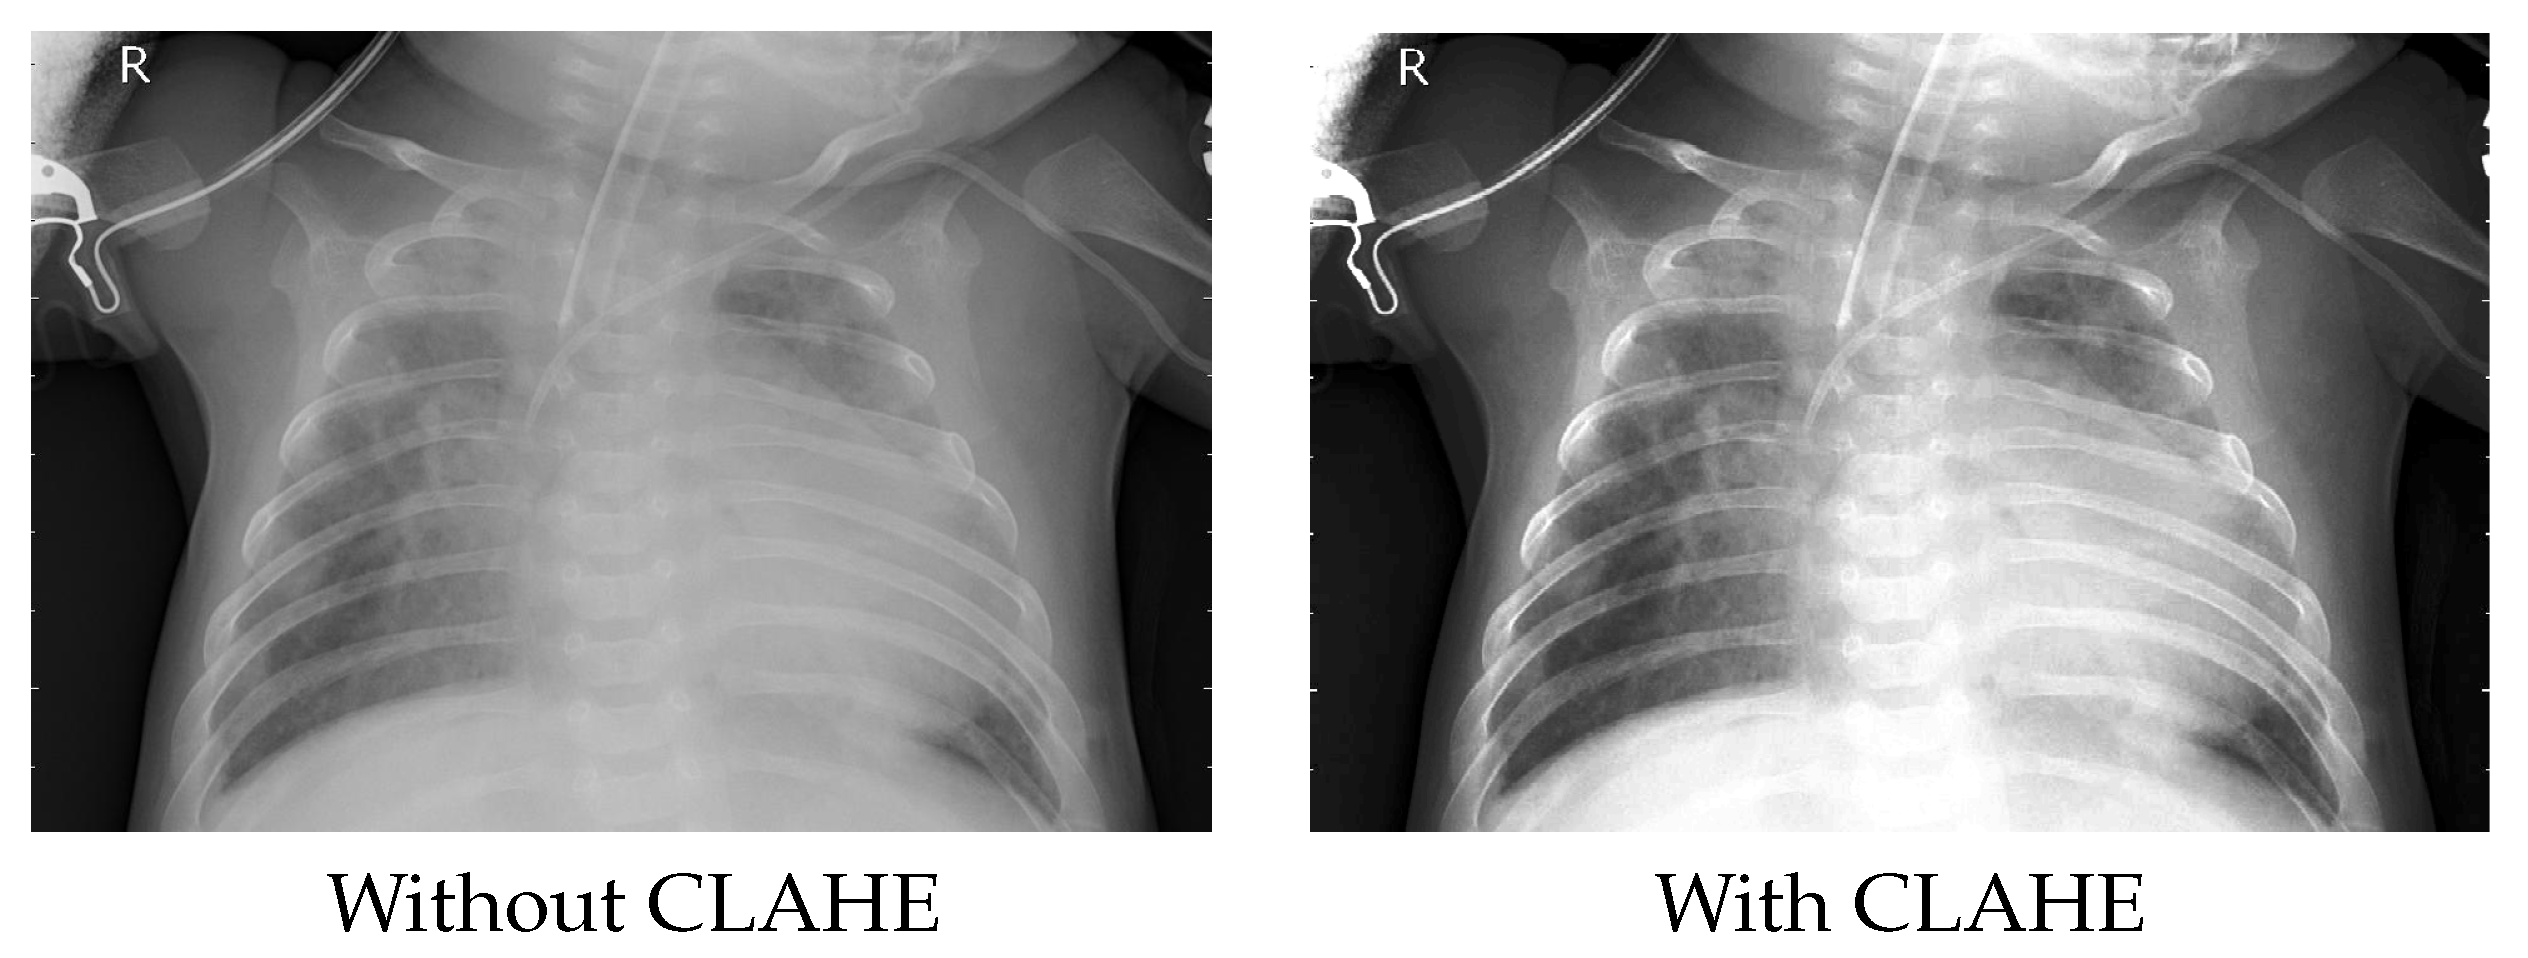

3.1.2. Improving the Image Quality

- Zuiderveld, K., VIII. Contrast limited adaptive histogram equalization. Graph. Gems 1994, 474–485. Available online: https://cir.nii.ac.jp/crid/1570009751230513024 (accessed on 21 August 2022).